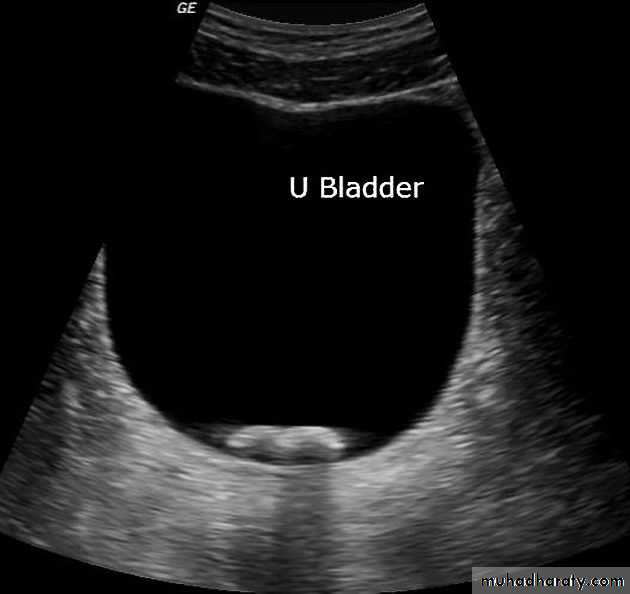

• The bladder is centrally located and should be smooth in outlines.

Often show normal smooth indentations from above due to uterus or sigmoid colon.

-After micturition the bladder should be empty apart from little contrast trapped in the folded mucosa.